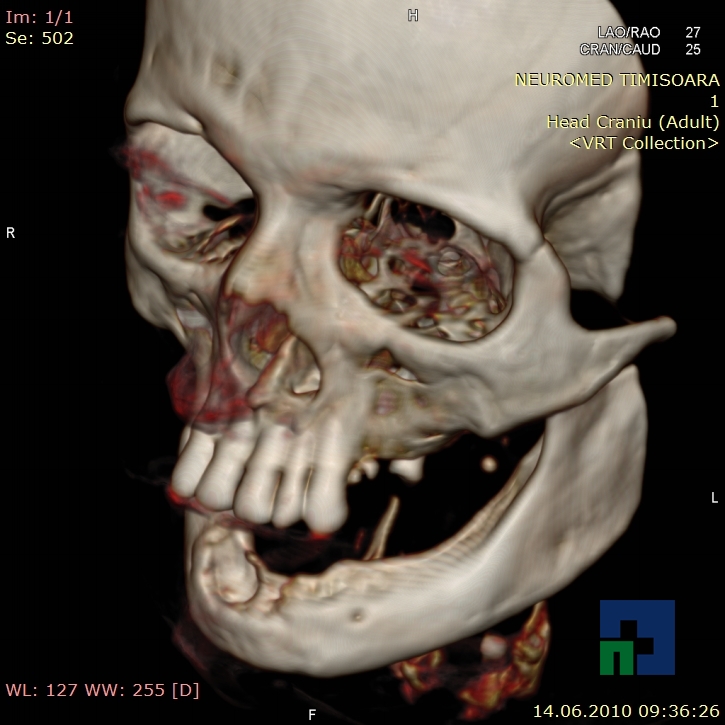

- Diagnosticul fracturilor:

-

- Unice

- Multiple

- Cu înfundare

- Complexe cranio-sinusale

- Complexe cranio-etmoidale

- Complexe cranio-orbitare

- Complexe cranio-faciale